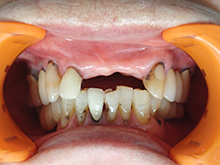

A G C

ガルバノテクニックを用いて作製されるセラミックであり、純金を用いる事によって生体親和性に優れ、歯肉にもやさしく、最適な適合精度と最適なマージン適合性が得られます。

症 例